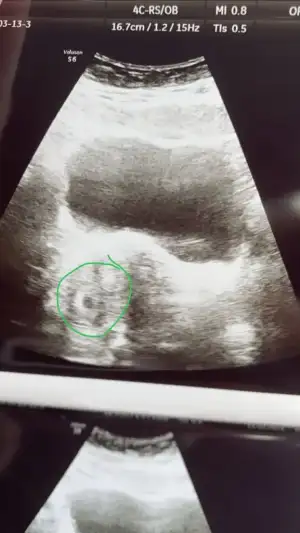

Merhaba, Vajinal muayene mi acaba? Bir de baska doktora gitseniz iyi olacak gibi sankiMerhaba arkadaşlar benim son sat 5 Şubat ve Bat 4 Martidi.

8 martta testim pozitif çıktı .

Bunun üzerine 10 martta doktora gittim ve bhcg 4430 çıktı . fakat kese yoktu

13 martta tekrar gittik ve ekteki şekilde minik bir keseye benzettiği görüntü çıktı fakat yine yolk vs yoktu .

10 gün sonra tekrar gel dedi ama içim içimi yiyor

hiç mide bulantısı vs yok sadece ağrısı ve gaz .

Bu durumu yaşayan var mı aranızda?

ilk gebeliğim , 34 yaşındayım . Ve kiloluyum .

Karından yapıldı vajinal acele etmeyelim dediMerhaba, Vajinal muayene mi acaba? Bir de baska doktora gitseniz iyi olacak gibi sanki

Karından gorunmeyebiliyor, ilk zamanlar vajinadan bakmak daha iyi, net olyor o zaman, hem de dis gebelik vs onlar daha iyi saptanabiliyor aslinda. Istersen baska doktora bir git, vajinal bakilsin hem.Karından yapıldı vajinal acele etmeyelim dedi